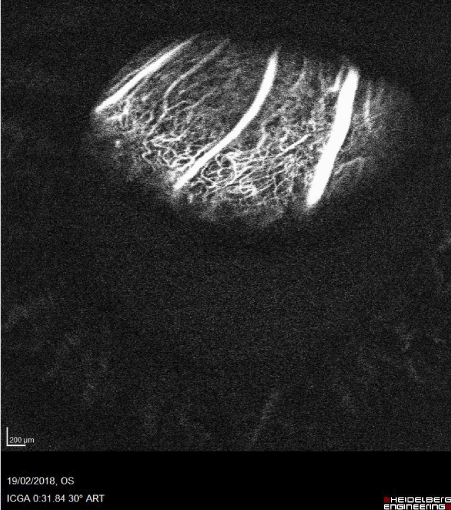

Fluorescein and indocyanine Angiography showed an irregular hyperfluorescence with atypical circulation (Figure 5). Lesion was partially explorable due to the nystagmus. The clinical and imaging features suggested a diagnosis of jumbo choroidal amelanotic melanoma.

Figure 5. Indocyanine Angiography. Atypical circulation